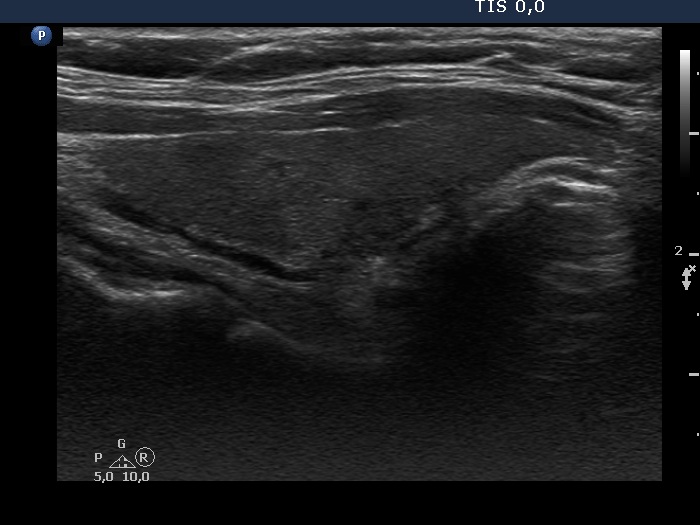

Consecutive patients with the final diagnosis of Hashimoto's thyroiditis - case 34 (927) (ultrasonographic picture 2)

Right lobe, longitudinal scan.